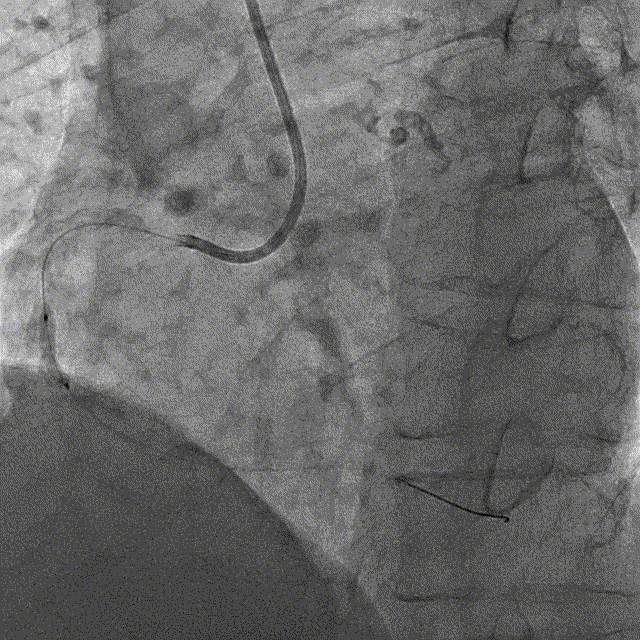

冠脉内介入治疗